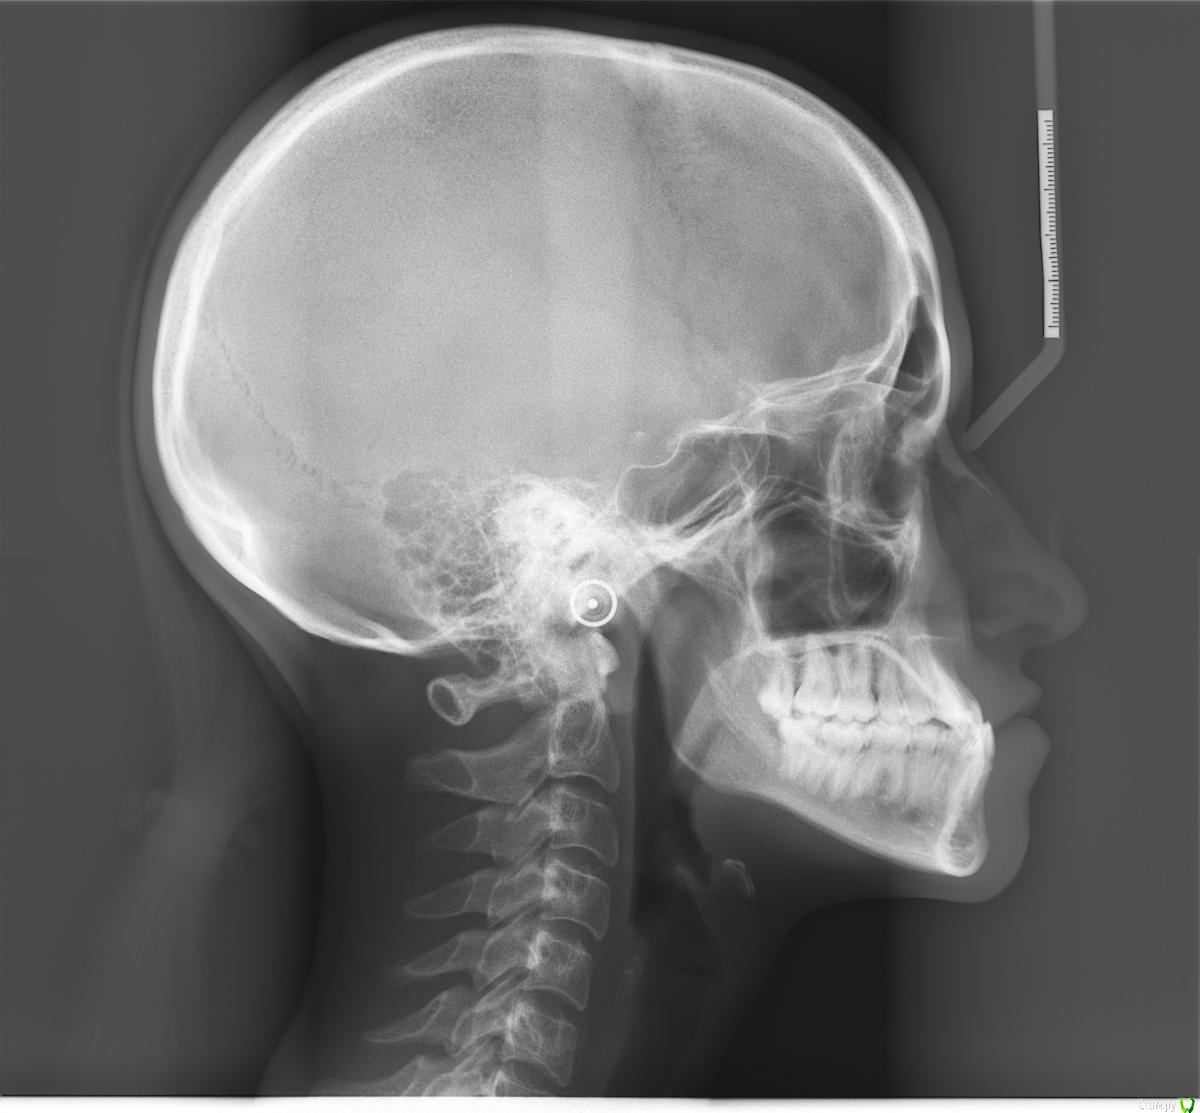

Opdihatop Опубликовано 10 декабря, 2016 Поделиться Опубликовано 10 декабря, 2016 Добрый вечер, коллеги! У меня вопрос к тем, у кого опыта по MEAW больше, чем у меня. Пациентка, 24 года, на данный момент все зубы мудрости удалены, привычная окклюзия по резцам - край в край. Сам процесс я понимаю, но есть несколько нюансов, которые хотелось бы уточнить:1) Нивелировать ли просто фронт в/ч, как книжка пишет (просто поставить дугу и все), или все-таки немного дистализировать боковые участки? С одной стороны простое нивелирование ускорит процесс и облегчит перебрасывание резцов, с другой стороны я опасаюсь чрезмерной протрузии из-за выравнивания дистопированных клыков; но при этом дистализация усугубит 3-й класс.2)Какой высоты делать окклюзионные накладки, в книжке они минимальные, а мне как то хочется побольше, чтобы резцы разомкнуть почти край в край, но не испортит ли это биомеханику?Буду очень благодарен вам за помощь! Ссылка на комментарий

Opdihatop Опубликовано 10 декабря, 2016 Автор Поделиться Опубликовано 10 декабря, 2016 P.S.: на хирургию пациентка согласна, но только, если мультилуп не сработает. Ссылка на комментарий